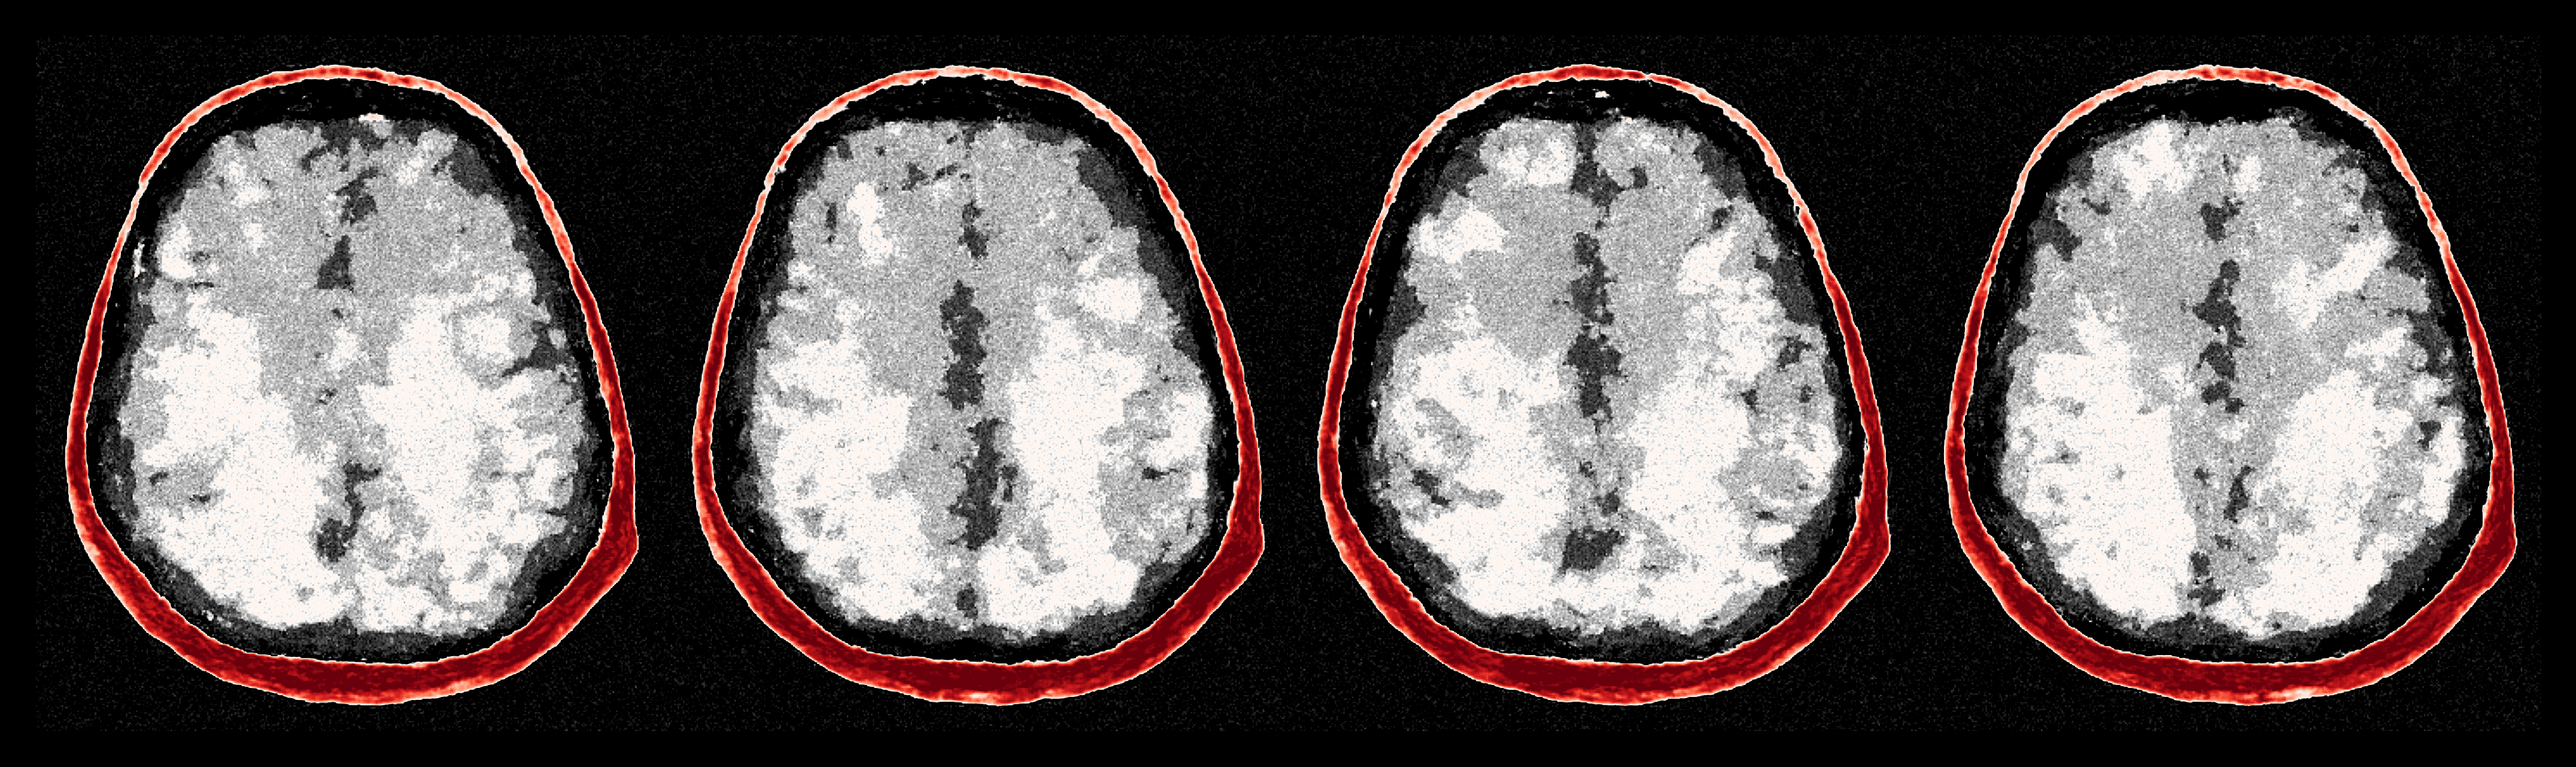

After the refinements of ASPIRE 2, significant improvements are evident in the posterior samples, particularly in capturing the structures within the brain tissue itself. The mean of these posterior samples, displayed in Figure 10, is clearly enhanced in resolution and details. We attribute these enhancements to the increased informativeness of the summary statistic in the second iteration compared to the information yielded by the initial iteration. A detailed inspection of the second summary statistic (shown in Figure 8) reveals more detail on the internal brain structures. Unlike the first summary statistic (cf. Figure 8), which primarily delineated the skull, the second iteration’s summary statistic better ‘illuminates’ the softer tissues within the brain, offering a more informative image for the posterior network. Thanks to accounting for the scattering at the skull, the acoustic illumination of the brain is improved significantly. Accurately resolving the skull structure is an important consideration as noted by [65].

As one can observe from Figure 10, the reconstruction quality improves for increasing number of refinements of ASPIRE. By virtue of the iterative recalculation of the score-based summary statistic, the method is progressively able to discern finer details within the brain albeit the updates become less pronounced as the number of refinements increases. We further illustrate this refinement by plotting posterior samples from all four ASPIRE iterations in Figure 21. Practically, a user of ASPIRE can decide on the number of refinements based on the amount of compute available or by refining until there are diminished returns on enhancements.